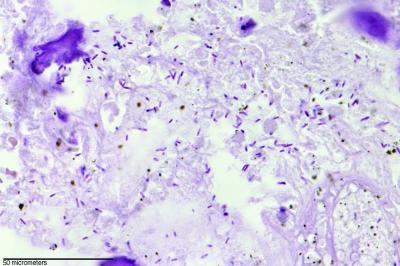

This is a gram stain of C. novyi-NT germination in a dog tumor.

The darker rod-shaped bacteria are visible throughout the image.

Credit: David L. Huso and Baktiar Karim of the Johns Hopkins

Department of Pathology.